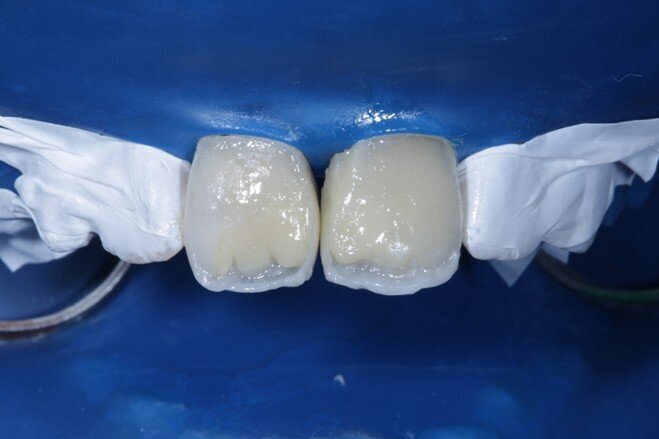

Desaturation was achieved by layering a deeper darker dentin [ A3 Dentin - Fig 12 ] inside and a lighter dentin [ A2 Dentin - Fig 13 ] shade over it in the shape of three mamelons. Incisal Halo was achieved by layering an Achromatic Enamel [clear translucent] shade around the mamelons [ Fig 14 ] and the A2 dentin shade on the incisal edge [ Fig 11 ]. Final layer of A2 Enamel shade was used covering the restoration in 0.5mm thickness so as to avoid too much translucency [ Fig 15 ]. Finishing and polishing were done using the 3M Soflex discs and spirals [ Fig 17 ] as recommended by the manufacturer.

Fig 15 Final enamel layer

Fig 18 After 48 hours of rehydration